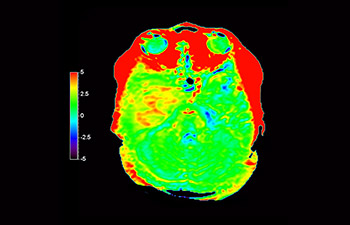

z użyciem metody 3D APT